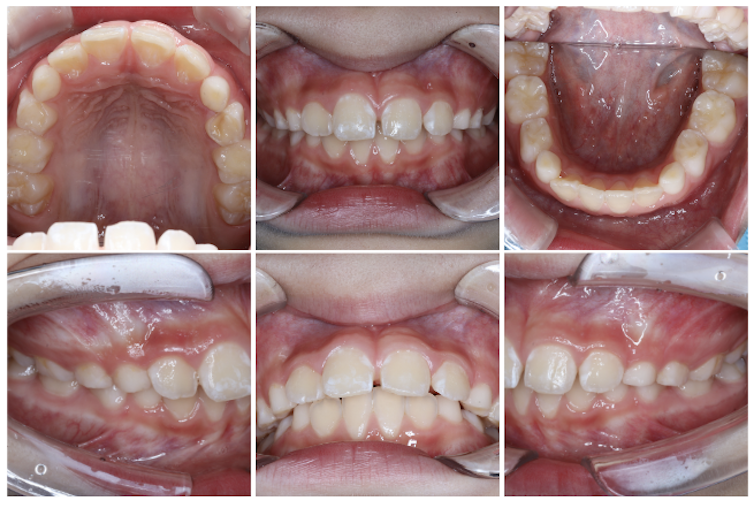

前歯のすき間(正中離開)を気にされていた親御様でしたが、定期検診の際に生え変わりとともに自然と閉じることもあることをお伝えしたところ、まずは経過を見ていくことになりました。

その後の定期検診で、過蓋咬合(上の前歯が下の前歯を深く覆いすぎてしまう噛み合わせ)が確認されたため、矯正についてお話しさせていただきました。その結果、マイオブレースによる矯正治療を8歳でスタートすることになりました。

噛み合わせの深さ(オーバーバイト)は、スタートから4ヶ月で5mmから2mmの数値改善が見られました!

以降も取り組みを頑張ることで理想的な数値を維持できており、開始から1年2ヶ月経った現在の写真を見ても、噛み合わせが浅くなってきていることが分かりますね。

また、親御様が気にされていた前歯のすき間も閉じることができました。

前歯の出具合(オーバージェット)は、9ヶ月で6mmから2mmの数値改善が見られました!

現在は1.5mmまで数値改善されています。